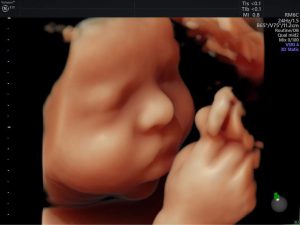

Mục đích của việc siêu âm thai là giúp bác sĩ thu thập thông tin, ...